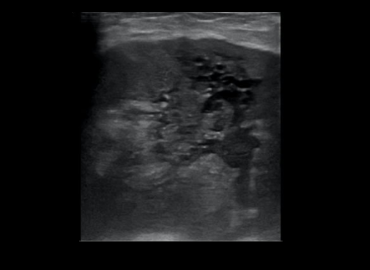

Paciente de 39 años consulta por cuadro de diarrea, dolor abdominal, fiebre y perdida de peso (10kg) de 2 meses […]